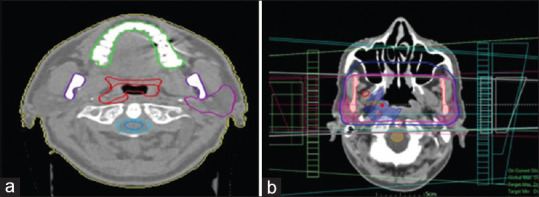

Background: Using three-dimensional conformal radiation treatment (3D-CRT) and helical tomotherapy (HT), this study examines and contrasts the dosage received by the mandible, maxilla, and teeth.

Methods: Sixteen patients with head-and-neck cancer (H and NC) were the subject of treatment planning at the Seyyed Al-Shohada Hospital in Isfahan, Iran. This study examined target coverage quality, exposure of healthy tissue, and radiation delivery effectiveness.

Results: In terms of a number of measures, including D2%, D50%, Dmean, V95%, conformity index (CI), and homogeneity index (HI) for the planning target volume (PTV) and D2%, D98%, Dmean, V95%, CI, and HI for the nodal PTV, HT showed considerable gains over 3D-CRT. The brainstem, D1cc, and D10cc received considerably lower maximum dosages in HT. Measurements of the right and left cochleas (Dmean, V55, and Dmax) revealed decreases in HT, with Dmean revealing the most significant variations. The Dmean and Dmax values for HT significantly decreased in constrictors as well. In terms of several HT-related indicators, the larynx, optic chiasm, optic nerves, oral cavity, mandible, thyroid, and parotid glands all showed considerable decreases.

Conclusion: The findings of the comparison of the two treatment approaches revealed that the HT method was more than 50% more effective than the 3D-CRT method in sustaining organs at risk (OARs) and the target volume dose. In general, dosimetric coverage, homogeneity, conformity indices, and the absence of cold and hot patches showed that HT produced targets with greater accuracy than 3D-CRT. In addition, HT outperformed 3D-CRT in protecting important structures (OARs). HT as a result has the potential to be a more effective method of treatment for those with H and NC and involvement of regional lymph nodes.